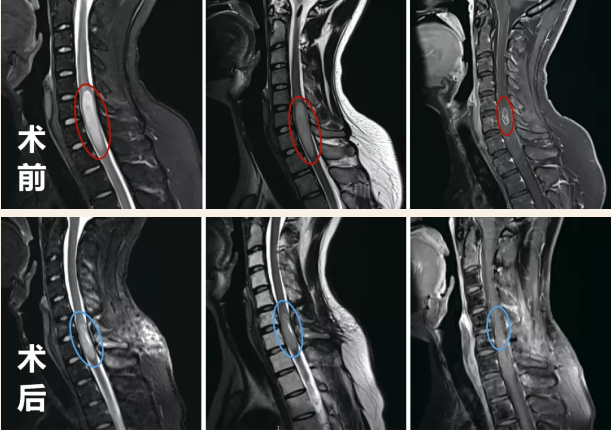

术前术后影像对比显示:脊髓内星形细胞瘤的瘤体强化部分被完整切除,肿胀效应减轻。